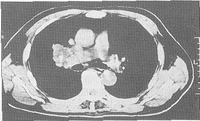

2例患者均成功完成经皮肺肿瘤局部置管术,无并发症,患者无特殊不适,一例患者在局部用药过程中出现一过性呛咳。肺部留置导管均保留了5天。患者经化疗后肺部肿瘤明显缩小(图2)。

图2 局部化疗术后43天,瘤体明显缩小

Fig 2 The tumor shrank apparently 43 days after regional infusion chemotherapy